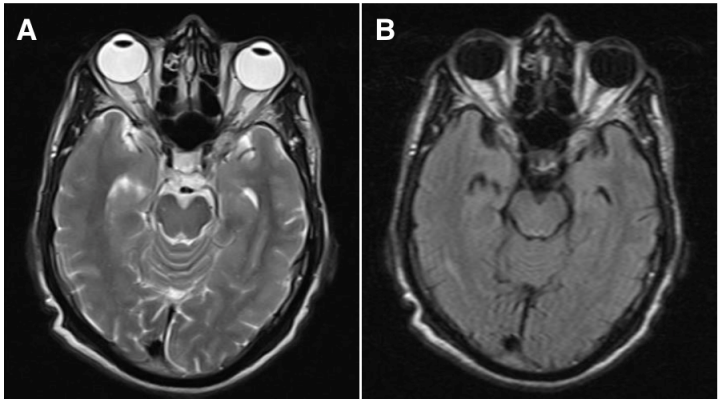

Hematological investigations showed that the hemoglobin was 9 gm% (normal: 12–15), platelet count was 255,000/mm3 (normal: 150,000–400,000), fasting plasma glucose was 106 mg% (normal: 80–120), blood urea was 34 mg% (normal: 15–40), serum Creatinine was 0.8 mg% (normal: 0.5–0.9), erythrocyte sedimentation rate was 28 mm at one hour (normal: 0–15), hematocrit was 89.8% (normal: 36–46), bleeding time was 2 minutes 05 seconds (normal: 0–7 minutes) and clotting time was 4 minutes 15 seconds (normal: 4–9 minutes). The lipid profile was normal. Peripheral blood smear showed microcytic hypochromic anemia with tear drop cells and Rouleaux formation. Total leucocyte count was normal with differential count showing eosinophilia (19%). The blood sample was negative for human immunodeficiency virus and hepatitis B virus. X-ray mammogram, sonomammogram and elastomammogram of the left breast in the craniocaudal and mediolateral oblique views showed a 2x 2.7 cm ill defined hypoechoeic and hypolucent lesion with irregular margins in the retro areolar region with architectural alterations and nipple retraction. The axillary lymph nodes were enlarged with the largest measuring 1x 0.9 cm. Ultrasound abdomen and magnetic resonance imaging of the head and orbit (axial T2-weighted sequence, Figure 3A [Fig. 3]; fluid-attenuated inversion recovery sequence (FLAIR), Figure 3B [Fig. 3]) did not show any secondary mass lesions.

Figure 3: Magnetic resonance imaging of the brain and orbit by axial T2-weighted sequence (A) and fluid-attenuated recovery (FLAIR) sequence images (B) do not show any lesions in the choroid, optic nerve or orbit on both sides.